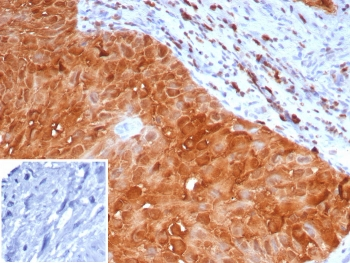

Cathepsin D Antibody

| Description | Cathepsin D Antibody |

| Tested applications | FC, ICC, IHC, IP, WB |

| Reactivity | Human, Mouse |